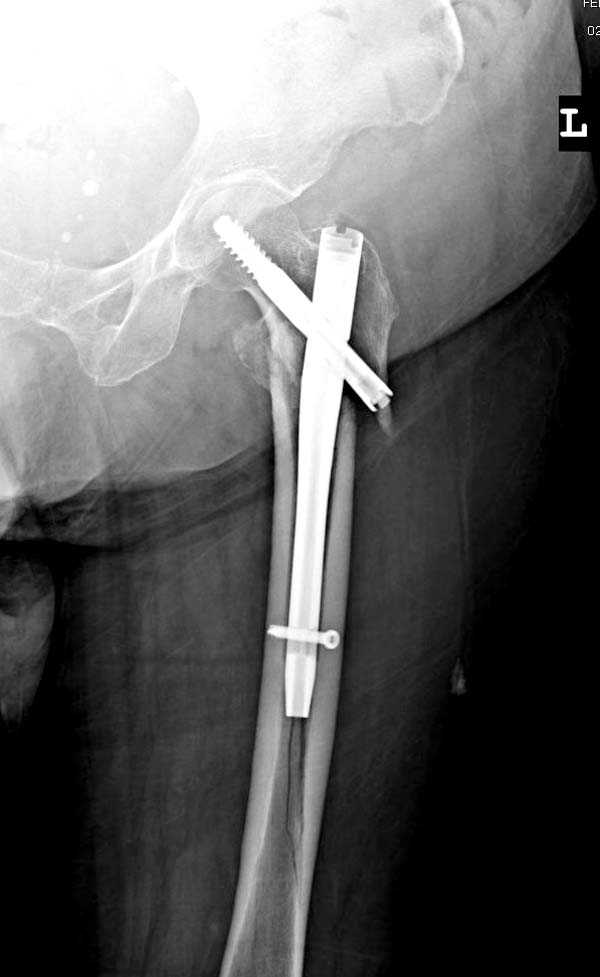

При первом послеоперационном поликлиническом осмотре больная предъявила жалобы на боли в бедре. В серийных снимках обнаружен продольный перелом верхнего отдела бедра.

Считаем, что техническая ошибка произошла во время установки гвоздя, когда рассверливанию канала не уделили должного внимания. Канал остался узковат, и гвоздь был забит с силой. Полная нагрузка конечности приостановлена на две недели, и боли в конечности изчезли. Больная начала нагрузку и перелом срастается.-- Djoldas Kuldjanov, M.D.Associate ProfessorDepartment of Orthopedic SurgerySt. Louis University

Мне тоже представляется, что это не единственная проблема. Продольные трещины заживают легко и быстро. Интересно, почему увеличился варус и

появилась медиализация дистального отломка.

Мне думается, что варусное положение проксимального отломка на последующих снимках не более чем проекционный феномен. Раскол же диафиза вдоль, наверняка, связан с чрезмерно насильственным введением штифта. Вообще, при реверсивных, да и обычных вертельных переломах, многие давно отказались от короткой Гаммы в пользу long-версии. Но в любом случае надо быть на 100 уверенным в подготовке канала.

Перелом А3, подвертельный, вероятно, на длинной версии гвоздя такого бы не произошло

eto nestabil'nui perelom. nado bylo stavit' gamma long. kanal uzkii (bylo vidno). mesiaz ne nagrujat', vse srastetsia!